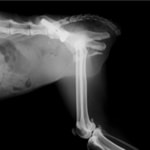

症例3:キルシュナーワイヤーのピンニングによる整復

ペルシャ猫 11ヶ月齢 雄

他院にて左大腿骨遠位の成長板骨折(salter-harrisⅠ型)が認められており、治療相談を目的として来院。当院にて、キルシュナーワイヤーを用いたピンニングにより骨折部位の整復を行いました。術後の経過は良好で、現在も経過観察中です。

術前レントゲン

術後レントゲン